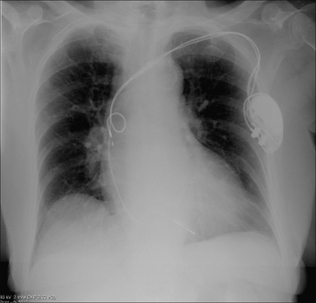

POST-IMPLANTATION CXRS17

Why obtain a CXR? It is obtained in order to make sure that all is well. A clinically unsuspected complication from pacemaker insertion is infrequent. Nevertheless, complications do occur.

CXR practice varies between hospitals and clinics. Most physicians obtain a frontal CXR soon after insertion of the pacemaker. Others obtain lateral and frontal radiographs. If an atrial electrode is utilised then a lateral CXR is usually needed so as to ensure that the tip of the electrode (sited in the right atrial appendage) points towards the anterior wall of the thorax.

image

Figure 12.5 Optimal electrode positions. Dual chamber pacemaker. Pacemakers tend to be introduced from the left side in right-handed patients.